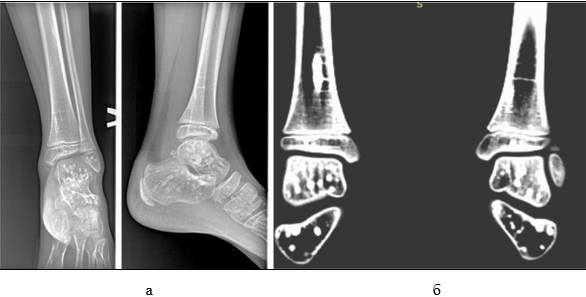

2024 год. Пациент Н., 7 лет, обратился с жалобами на боли (по шкале ВАШ 5 баллов) в левом голеностопном суставе. Со слов пациента: упал, подвернув левую ногу вовнутрь. Осмотр: контуры голеностопного сустава сглажены, отечны (+3см), цвет кожных покровов физиологической окраски. Пальпация области наружной лодыжки болезненная. Подвижность в левом голеностопном суставе активная и пассивная ограничена из-за отека, при этом активная - болезненная, пассивная - безболезненна. Тест с осевой нагрузкой положительный: поколачивание по пяточной кости вызывает болевые реакции в области наружной лодыжки. На рентгенограмме в двух проекциях (рис. 3а) грубой костной патологии не выявлено.

Рис. 3. Пациент Н., 7 лет. Рентгенограмма левого голеностопного сустава в двух проекциях (а); компьютерная томограмма обоих голеностопных суставов (б) (архив автора)

Выставлен диагноз: «Частичное повреждение связочного аппарата левого голеностопного сустава». Назначено лечение: иммобилизация фиксирующей повязкой, холод в течение суток, двигательный покой. С учетом наличия очагов склероза на рентгенограмме рекомендовано для уточнения диагноза сделать компьютерную томограмму (КТ) голеностопных суставов, контрольный осмотр с результатами назначен через 7 дней.

Заключение рентгенолога (рис. 3б): КТ картина соответствует остеопойкилии.